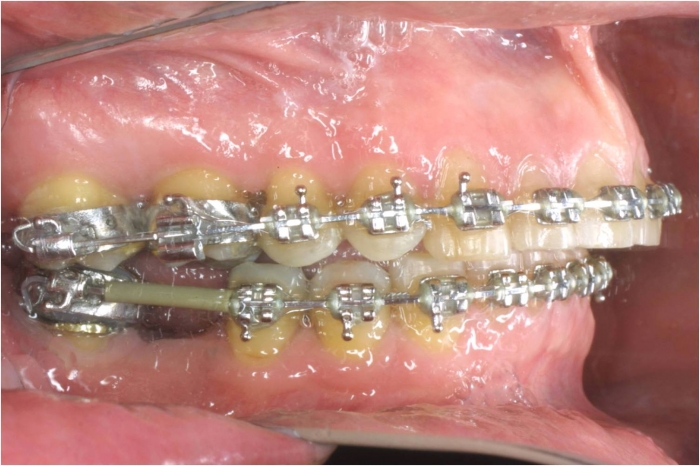

Mordida inicial